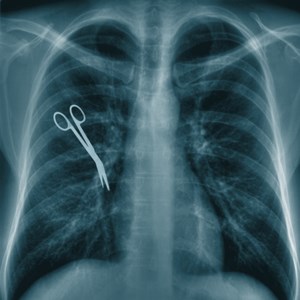

• Interesting Medical Error Fact

Tools are more likely to be left during emergency surgery or when the procedure changes unexpectedly

• Doctors leave sponges and other medical devices inside of their patients about 6,000 times a year.[12]